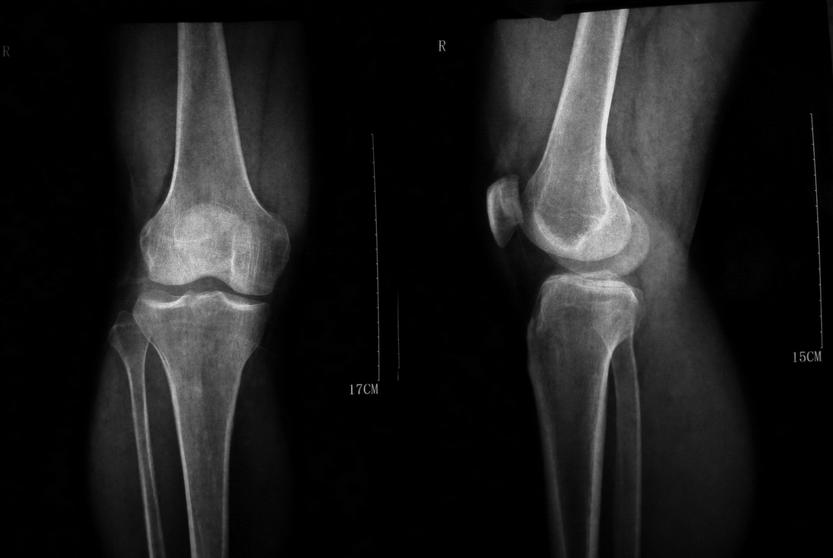

X线示:双膝关节边缘及髌骨底呈唇样改变,相应关节面不光整;膝关节间隙呈内窄外宽。

(图:刘女士初到院时膝关节透视图)